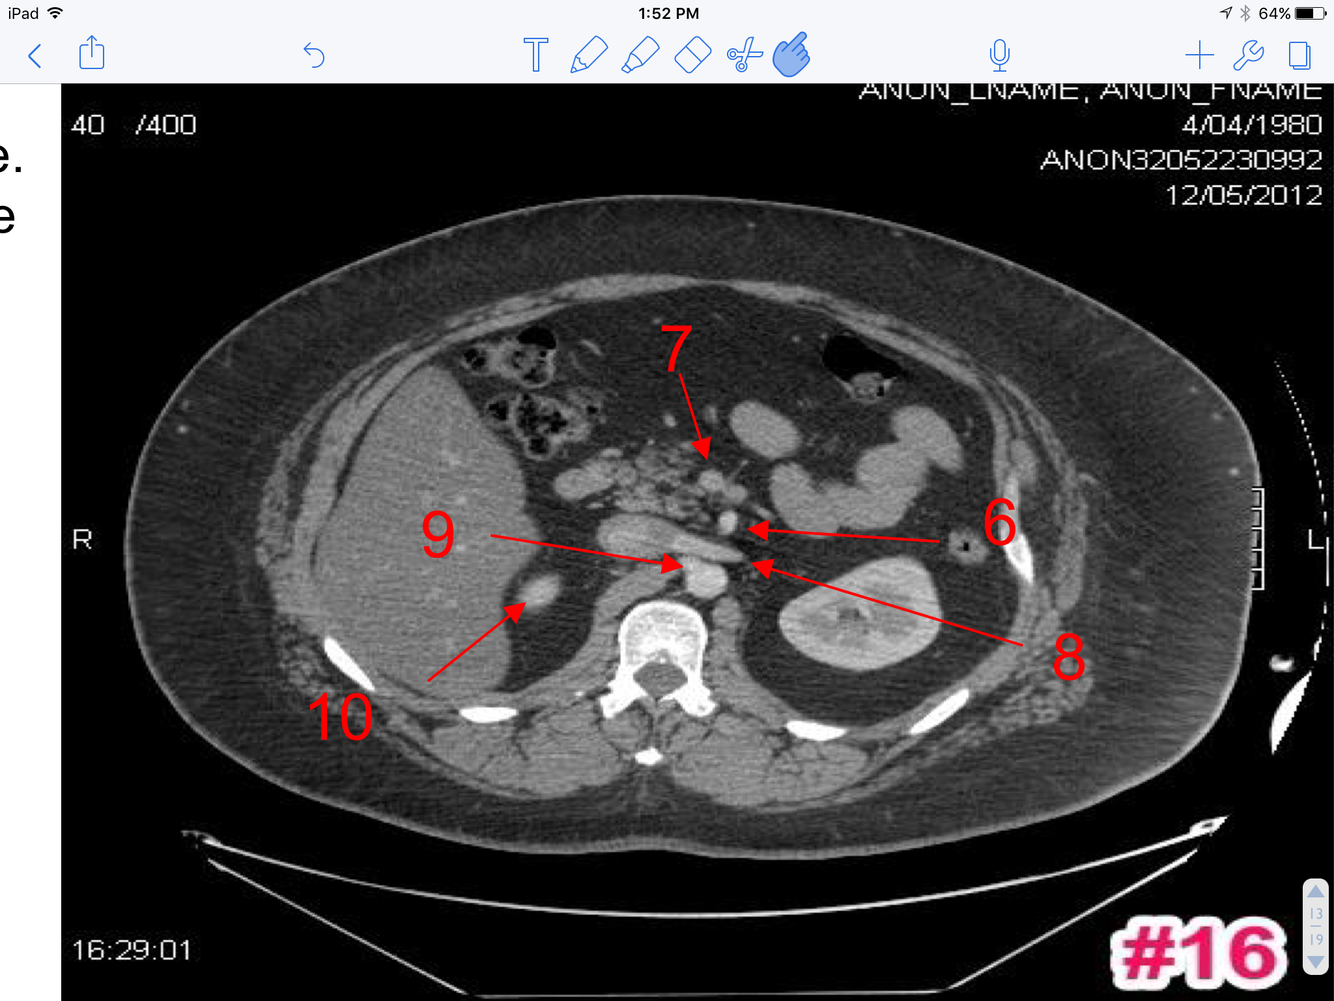

16

A

1. Transverse colon

2. Ascending colon

3. Rt renal pelvis